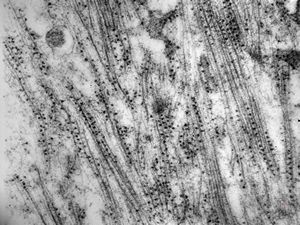

F,32y. | transversally sectioned skeletal muscle cell

mouse skeletal muscle cell - transversal section